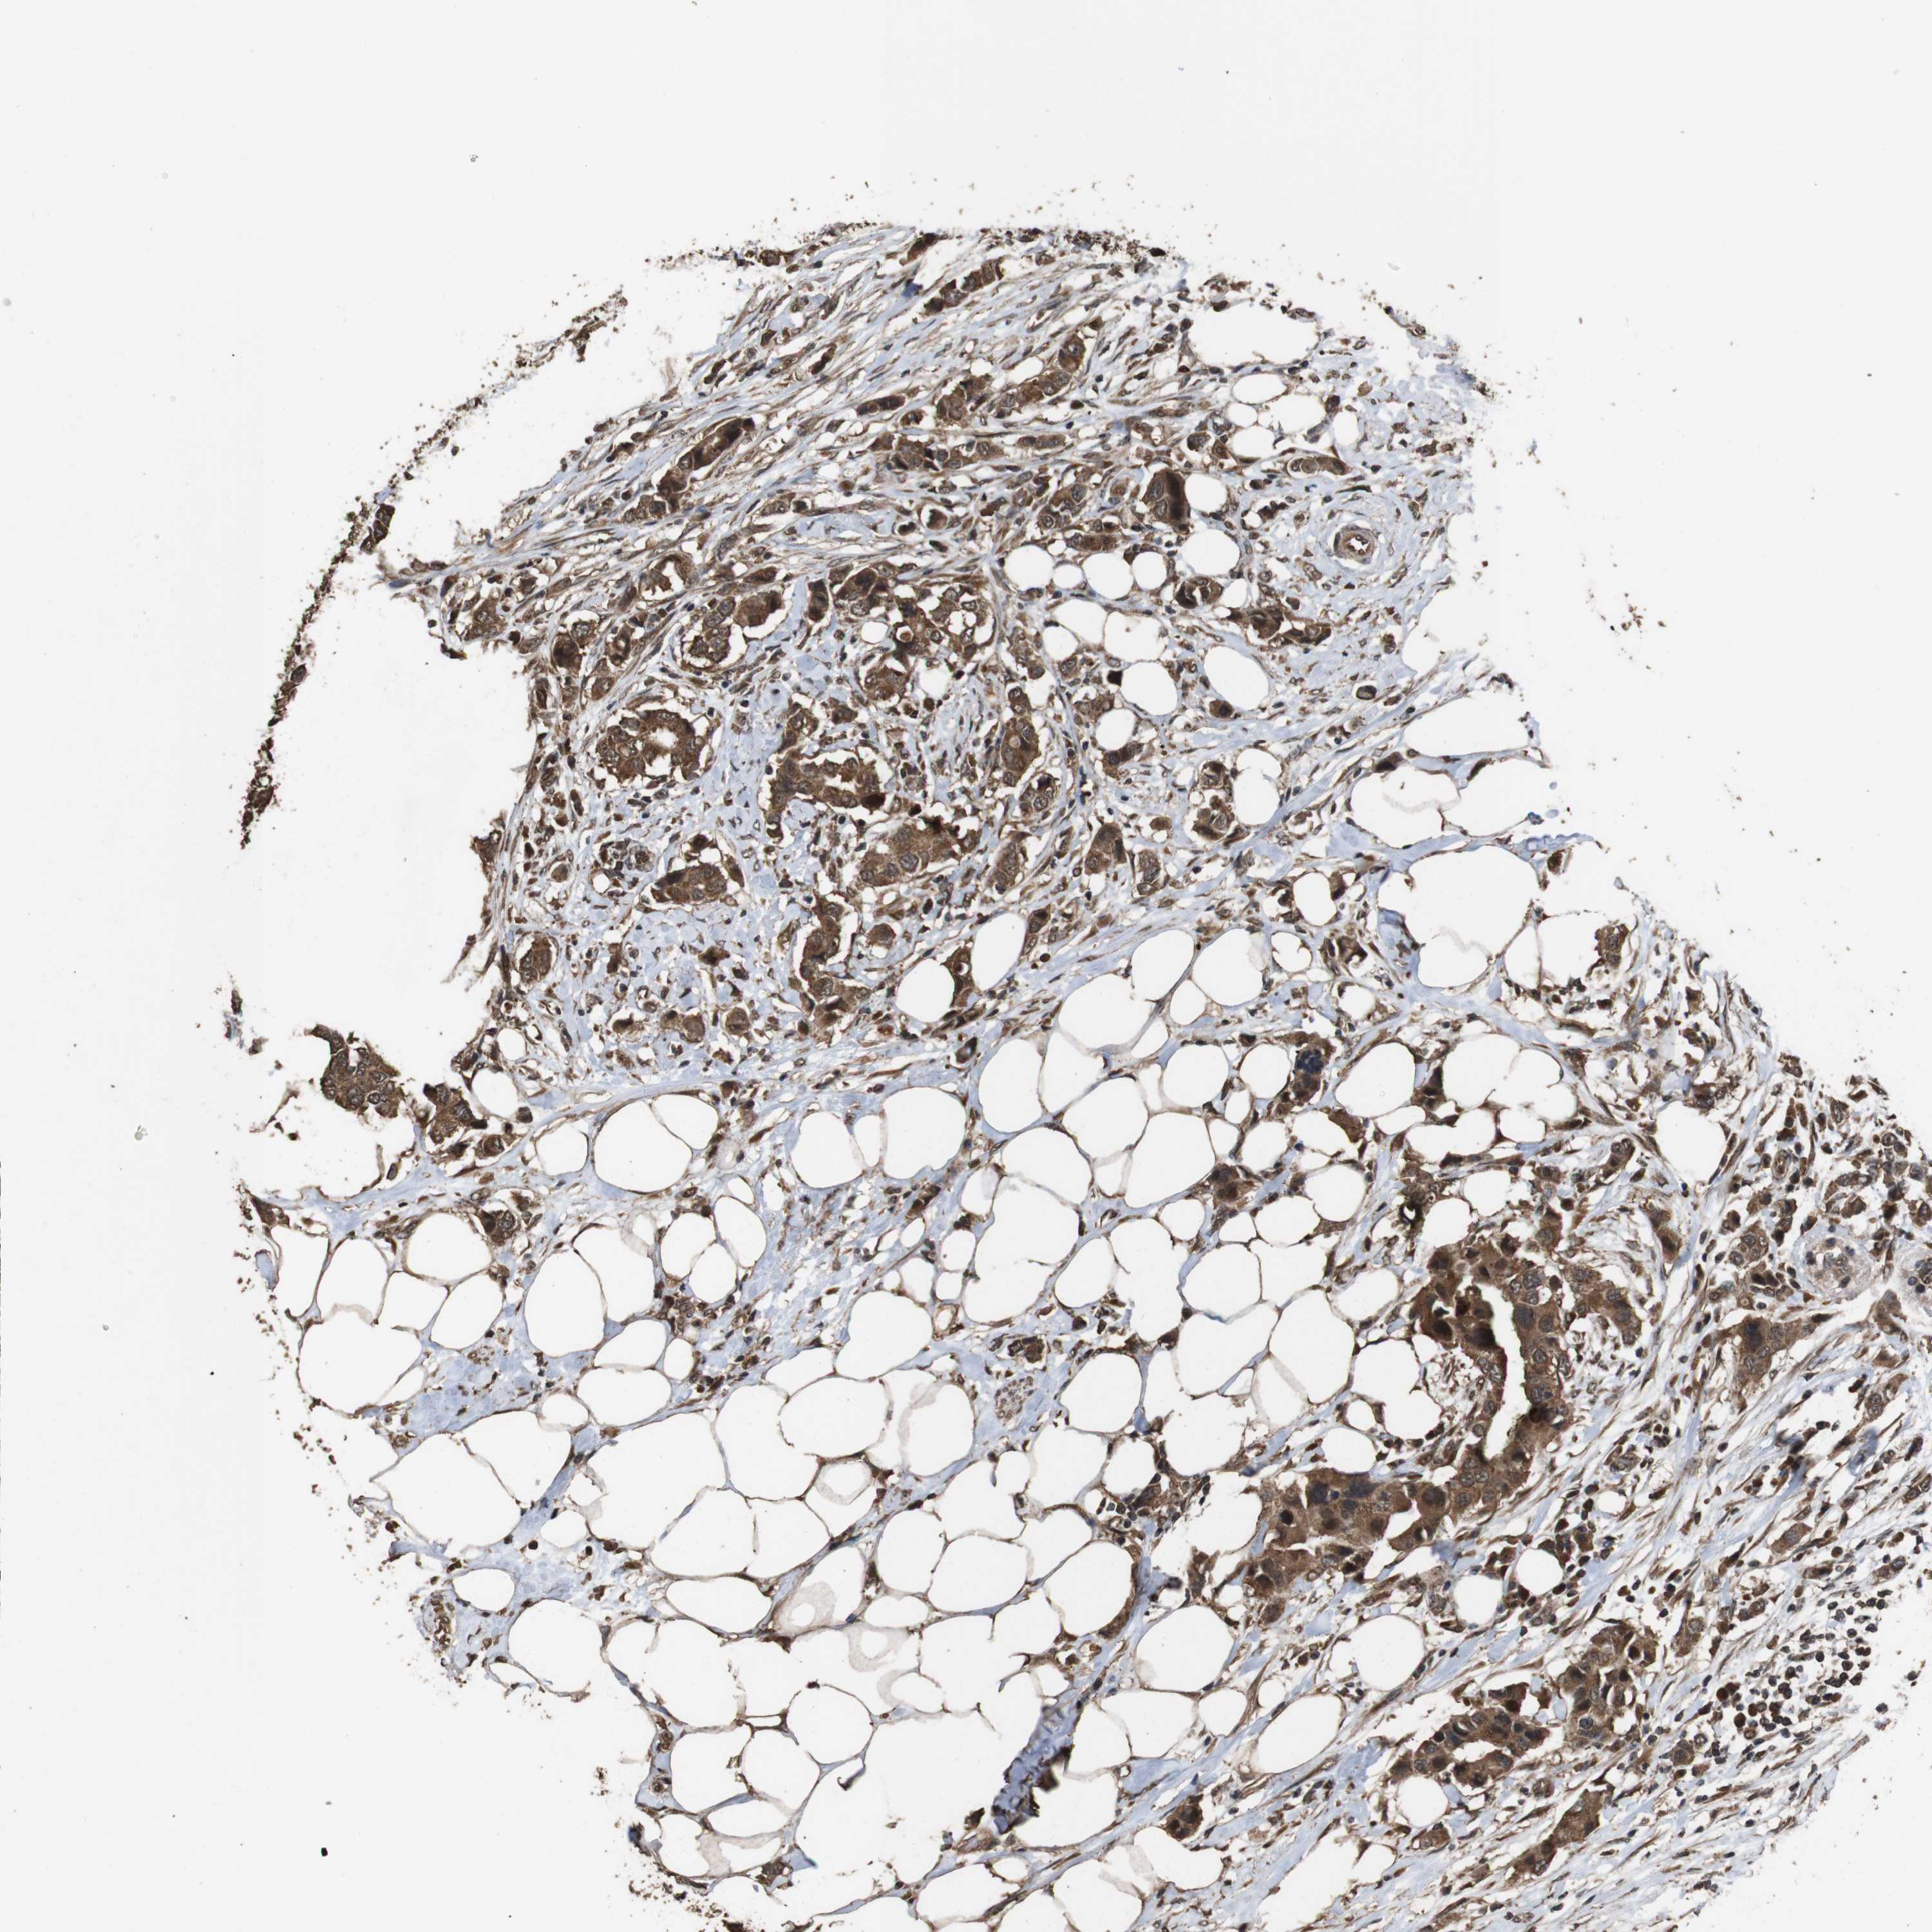

CANCER BREAST CANCER Show tissue menu

BRCA TCGA BRCA VALIDATION PROTEIN EXPRESSION